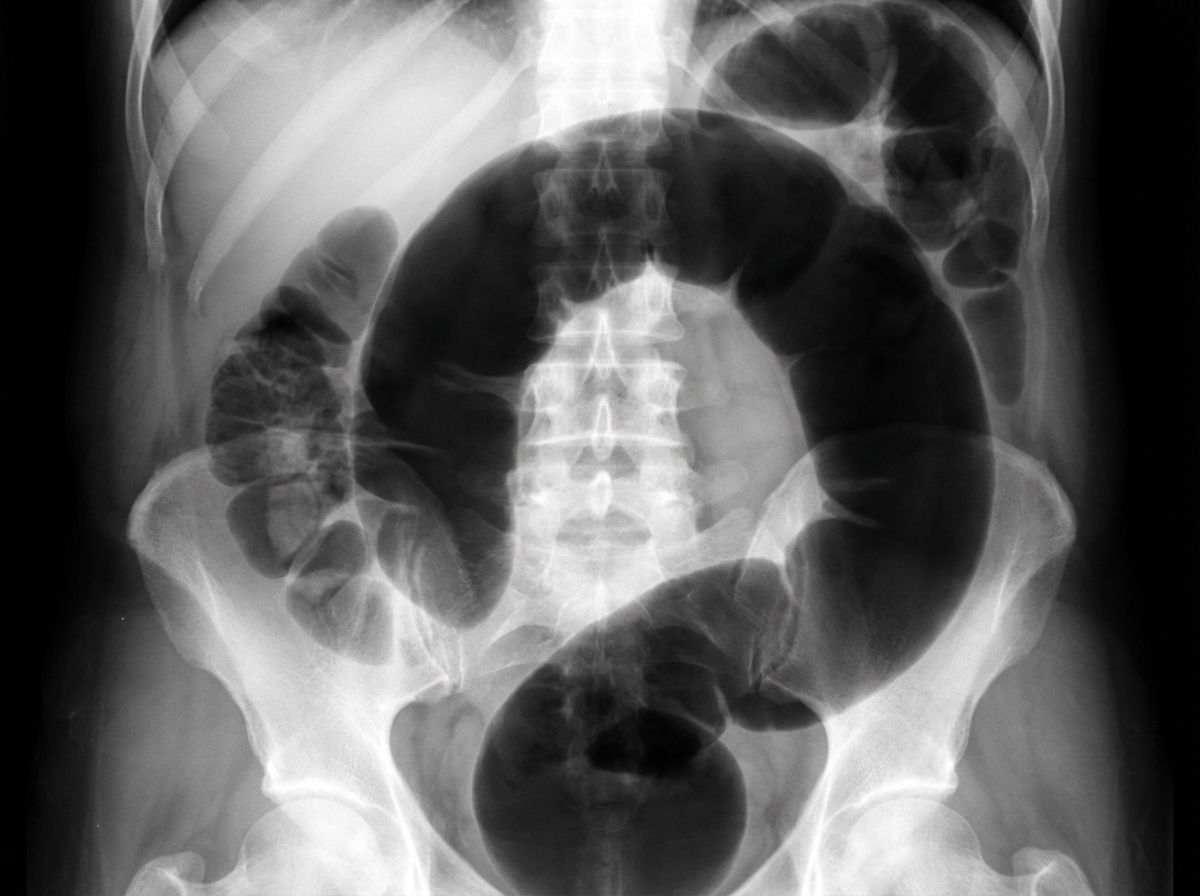

An institutionalized 65-year-old man is brought to the emergency department because of abdominal pain and distension for 12 hours. The pain was acute in onset and is a cramping-type pain associated with nausea, vomiting, and constipation. He has a history of chronic constipation and has used laxatives for years. There is no history of inflammatory bowel disease in his family. He has not been hospitalized recently. There is no recent history of weight loss or change in bowel habits. On physical examination, the patient appears ill. The abdomen is distended with tenderness mainly in the left lower quadrant and is tympanic on percussion. The blood pressure is 110/79 mm Hg, heart rate is 100/min, the respiratory rate is 20/min, and the temperature is 37.2°C (99.0°F). The CBC shows an elevated white blood cell count. The plain abdominal X-ray is shown in the accompanying image. What is the most likely cause of his condition?

Large bowel obstruction